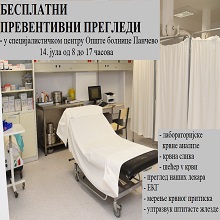

У оквиру редовне превентивне акције Министарства здравља Републике Србије, и ове недеље смо у специјалистичком центру Опште болнице Панчево организовали акцију превентивних прегледа која је омогићила нашим грађанима да провере своје здравље и тиме значајно утичу на превенцију даљем развоју болести, такође пацијенти који су желели могли су се вакцинисати против сезонског грипа. |

И ове недеље организујемо акцију превентивних прегледа. Позивамо грађане да дођу у специјалистички центар Опште болнице Панчево, у недељу, 6. октобра од 8 до 17 часова и провере своје здравствено стање. Прегледе могу обавити сви грађани Панчева и околине, без здравствене књижице. Акције које спроводи Министарство здравља за циљ имају рану дијагностику и промоцију превенције као најефикаснијег начина бриге о здрављу. |

И овог викенда, у оквиру акције Министарства здравља, у Панчеву су одржани бесплатни превентивни прегледи. Сви грађани, укључујући и оне без здравственог осигурања, имали су прилику да провере своје здравствено стање. |

у недељу 15. септембра 2024. године, у периоду од 08:00 до 17 часова, одржаће се превентивни прегледи у здравственим установама целе земље, као и у Општој болници Панчево. |

Још једна у низу акција превентивних прегледа у организацији Министарства Здравља Републике Србије одржаће се у Општој болници Панчево, 8. септембра 2024. године од 08 до 17 часова. |

Без заказивања и здравствене књижице и ове недеље грађани Панчева могли су да преконтролишу своје здравље. Превентивни прегледи битни јер се у већини случајева болест открије на време и може да се излечи и контролише на адекватан начин. |

Акцијом бесплатних превентивних прегледа, које спроводи Министарство здравља, 14. јула 2024.године у периоду од 8.00 до 17.00 часова у специјалистичком центру Опште болнице Панчево организујемо превентивне прегледе. Сви наши грађани, и они без здравственог осигурања, биће у прилици да без заказивања и упута, брзо и ефикасно провере своје здравствено стање |

| У склопу акције превентивних прегледа које је организовало Министарство здравља и ове недеље прикључили су се Општа болница Панчево и Дом здравља. Наши најмлађи суграђани такође ове недеље могли су да се јаве педијатру, јер су прегледи били организовани и за њих. |

Овом приликом, 16. јуна 2024.године у периоду од 8.00 до 17.00 часова, и у специјалистичком центру Опште болнице Панчево биће организовани превентивни прегледи за све грађане. И они без здравственог осигурања биће у прилици да без заказивања и упута, брзо и ефикасно спроведу |

| После изузетног одзива током претходне акције када је у Србији прегледано око 23.000 грађана, Министарство здравља организовало је поново превентивне прегледе са циљем да се у раној фази болест дијагностикује, а тиме и да степен излечења буде већи. Грађани су у панчевачкој Општој болници и Дому здравља, као и у осталим здравственим установама широм Србије могли без упута, заказивања и здравственог осигурања да обаве основне лабораторијске анализе, измере крвни притисак, провере хормоне штитне жлезде и ураде тумор маркере простате. |

Услед великог интересовања грађана, Министарство здравља у недељу, 26.маја, наставља акцију бесплатних превентивних прегледа, коју спроводи у циљу ране дијагностике и промоције превенције. |

Грађани нису крили задовољсто што су на једноставан начин могли да провере своје здравље. Министарство здравља наставило акцију превентивних прегледа са циљем да се у раној фази болест дијагностикује. Грађани како у целој Србији тако у Општој болници Панчево су могли без упута, заказивања и здравственог осигурања уз преглед наших лекара измере крвни притисак, вредност шећера у крви, ураде ЕКГ и ултразвучни преглед абдомена. |

Акција бесплатних превентивних прегледа, које спроводи Министарство здравља у циљу ране дијагностике и промоције превенције као најефикаснијег начина бриге о здрављу, биће настављена у недељу, 19. маја од 8 до 17 часова, у специјалистичком центру Опште болнице Панчево. |